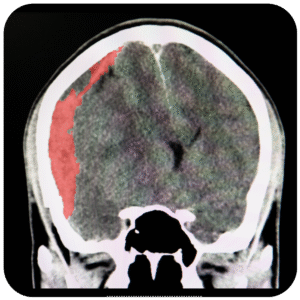

Meningocele

Es un defecto congénito en el cual los huesos de la columna no se forman totalmente, esto provoca un conducto raquídeo incompleto en el cual la médula y las meninges sobresalen de la espalda del niño.

Se corrige mediante un procedimiento quirúrgico llamado meningoplastia, que es el cierre quirúrgico del defecto.